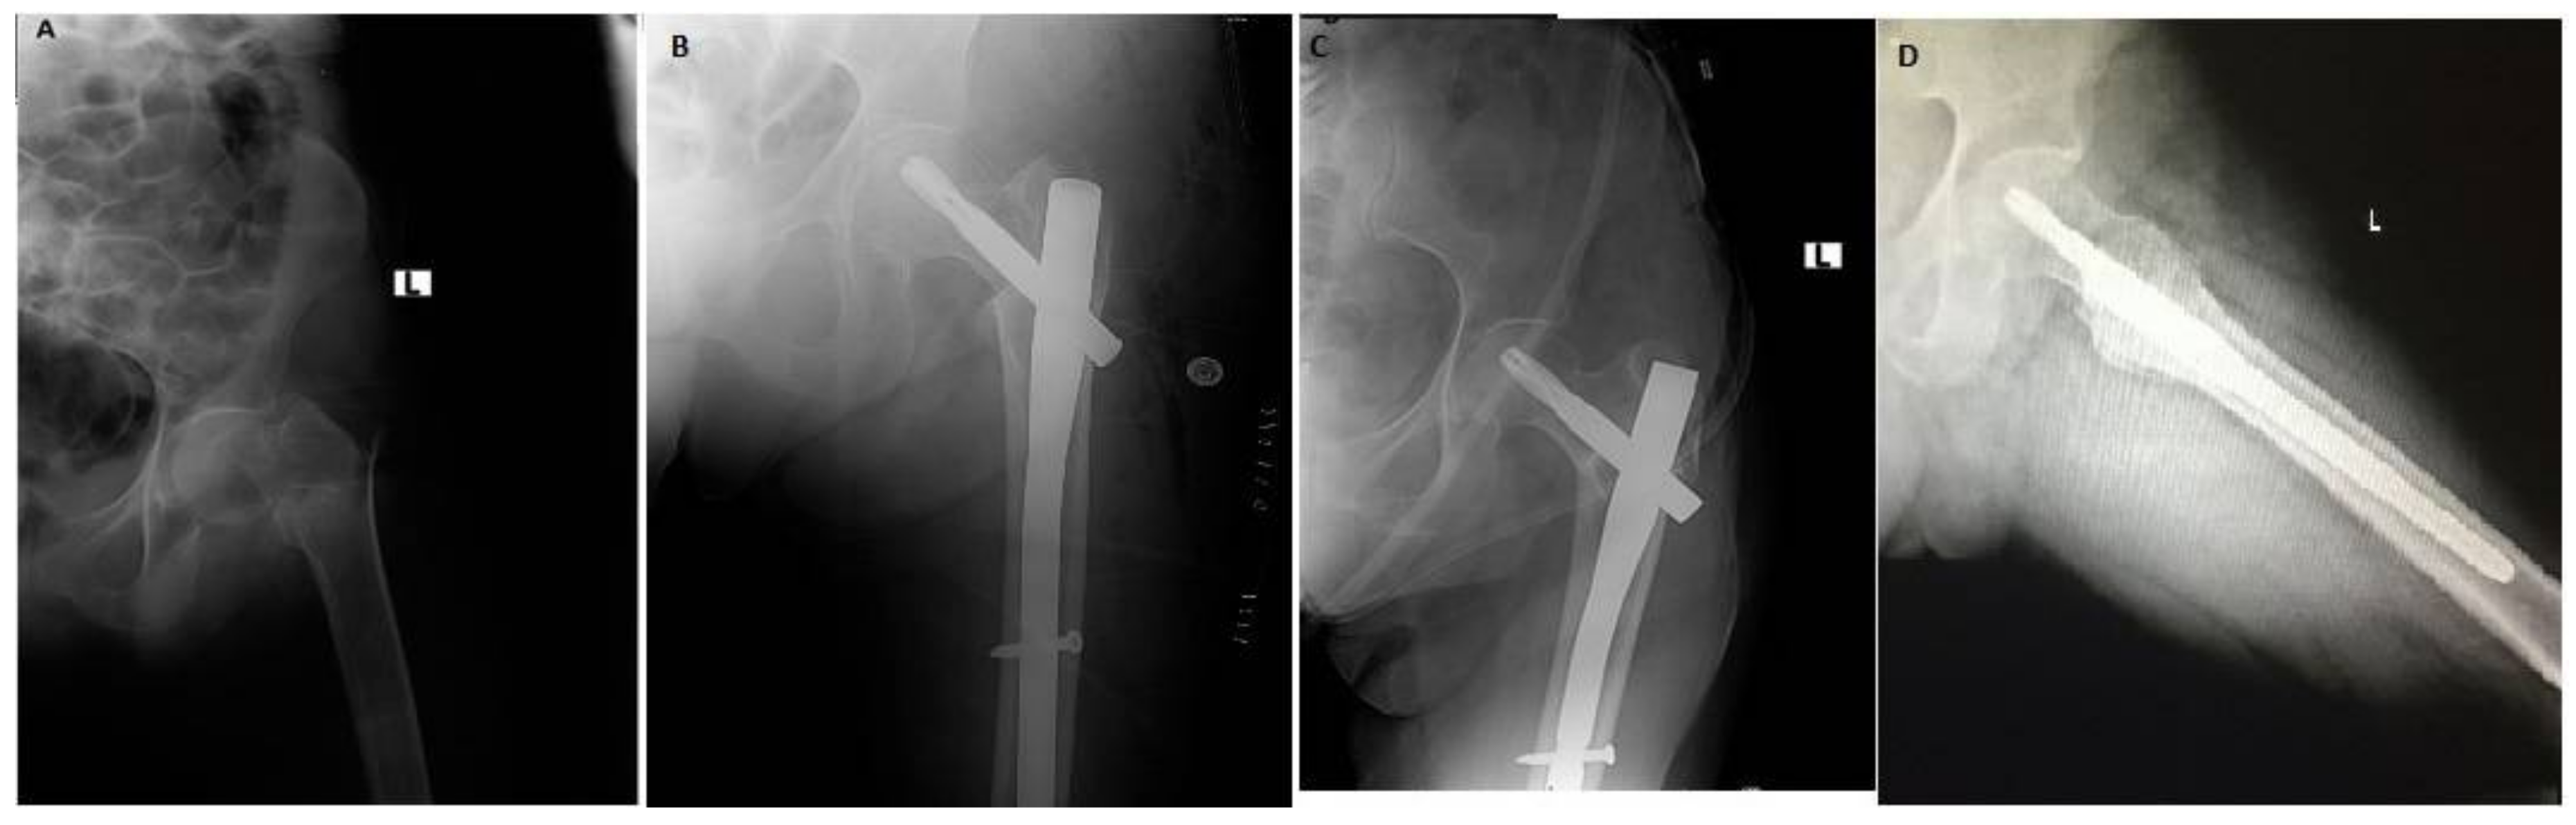

Functional and Radiological Results of Proximal Femoral Nail Antirotation (PFNA) Osteosynthesis in the Treatment of Unstable Pertrochanteric Fractures

2. Experimental Section

3. Results